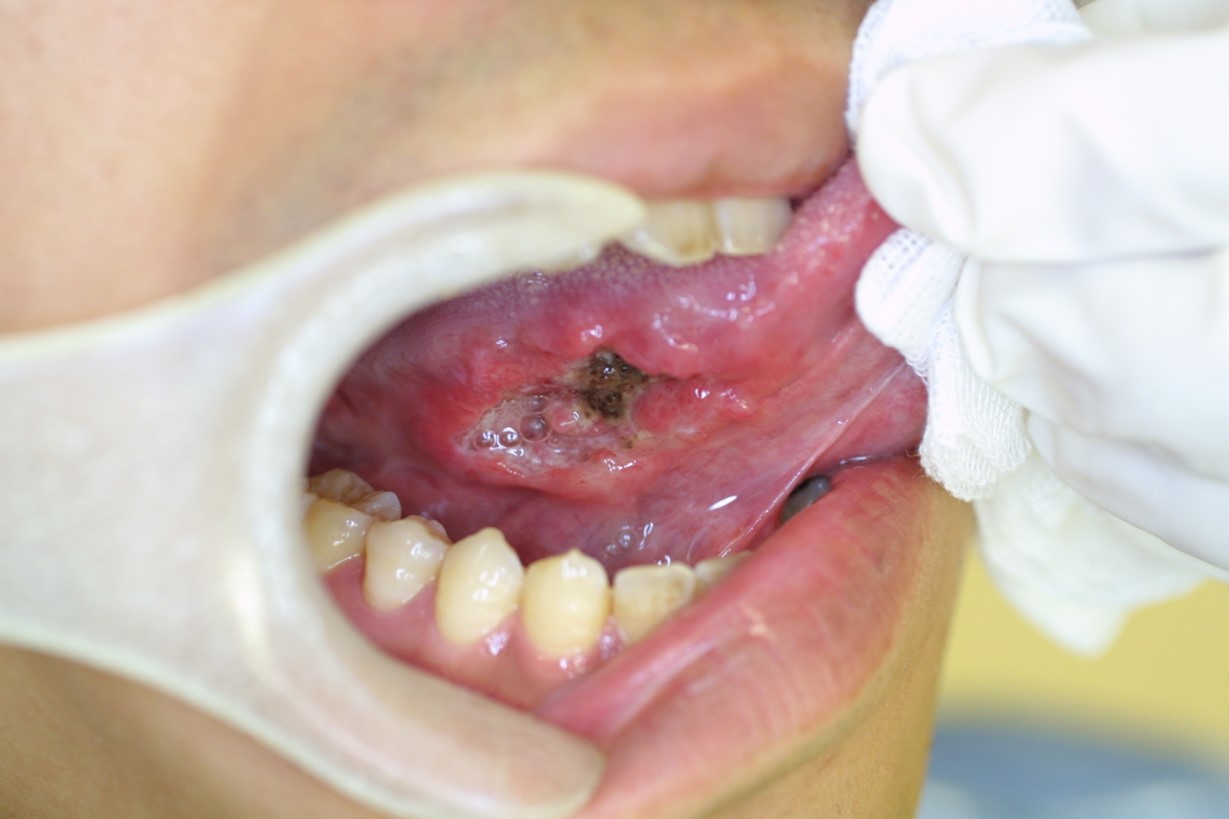

舌、歯肉、頬の粘膜などに赤斑(赤い部分)がある

前がん病変(がんになる前の状態の病変)の中に、紅板症というものがあります。この紅板症の約半分50%が、すでにがんになっていると言われています。紅のように赤く、少し、硬い感じがしたら要注意です。